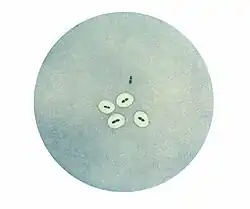

In 1900 Neufeld discovered bile solubility of pneumococci.[2] Addition of a small amount of ox bile to a pneumococcal culture results in complete destruction of the culture after a short incubation. This unique property became widely used to diagnose pneumococcal infections. Then, using immunological techniques, Neufeld discovered that there were three pneumococcal types. In the presence of type I antiserum type I pneumococci would swell, likewise types II and III in the presence of their specific antisera. Neufeld called this the quellung reaction, after the German word for swelling.[3][4] The quellung reaction allowed for easy laboratory identification of pneumococcal types.[5] Using Neufeld’s discoveries, Fred Griffith showed that pneumococci could transfer genetic information and transform one type into another.[6] Oswald Avery then found that the transforming substance was DNA. All of modern molecular biology has evolved from this work.